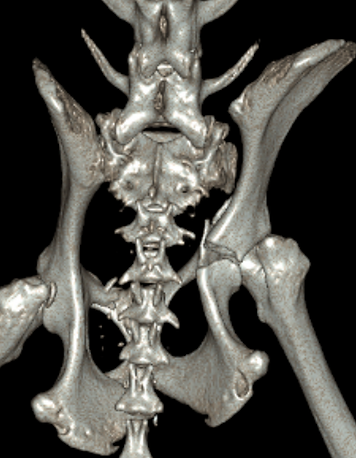

Radiographs (X-rays) are the primary diagnostic tool and may require special views to fully understand the fracture configuration. CT imaging is particularly useful for complex or joint-involving fractures.